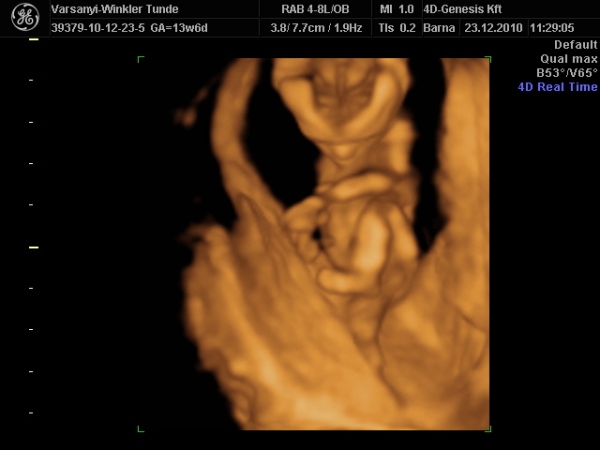

Bár tegnap a dokor bácsi azt mondta, hogy azért lassan vissza kellene vennem a lendületből, mert nem lesz jó vége. Manócska jól van, de tegnap nem tudtuk megnézni. Hasi uh-val próbálkozott, de pont úgy fordult, hogy csak a nagy kobakját láttuk

Gondolta, ha arra van a feje, akkor lentről lehet látni valamit a neméből.

Be is terpesztett rendesen, mint egy kis utcalány

Természetesen lánynak is látszott, bár azt mondta, hogy még ne éljük bele magunkat. A férjem le is tört egy kicsit, de nem vallotta volna be.Holnap reggel megyek AFP-re.